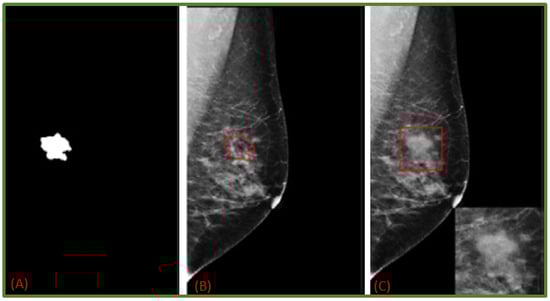

- Costa, A.C.; Oliveira, H.C.; Vieira, M.A. Data augmentation: Effect in deep convolutional neural network for the detection of architectural distortion in digital mammography. In Proceedings of the Brazilian Congress on Medical Physics, Santos, Brazil, 21–24 August 2019. [Google Scholar]

- Cha, K.H.; Petrick, N.A.; Pezeshk, A.X.; Graff, C.G.; Sharma, D.; Badal, A.; Sahiner, B. Evaluation of data augmentation via synthetic images for improved breast mass detection on mammograms using deep learning. J. Med. Imaging 2019, 7, 012703. [Google Scholar] [CrossRef] [PubMed]

- Zeiser, F.A.; da Costa, C.A.; Zonta, T.; Marques, N.; Roehe, A.V.; Moreno, M.; da Rosa Righi, R. Segmentation of masses on mammograms using data augmentation and deep learning. J. Digit. Imaging 2020, 33, 858–868. [Google Scholar] [CrossRef] [PubMed]